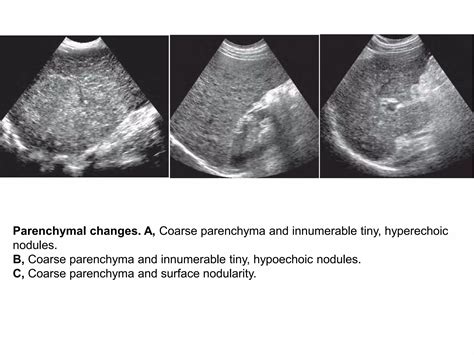

Secondly, the echogenicity or texture of the liver tissue is assessed. This refers to how the liver tissue reflects the sound waves. On an ultrasound, the liver appears as a gray, speckled pattern. A normal liver has a homogeneous, or uniform, echotexture. This means that the sound waves are reflected consistently throughout the liver. The liver tissue should be slightly more echogenic (brighter) than the kidney cortex (the outer part of the kidney). The blood vessels within the liver, like the portal veins and hepatic veins, appear as dark, anechoic (echo-free) structures. Any significant changes in echogenicity could indicate a problem, such as fatty liver disease (where the liver appears brighter) or cirrhosis (where the liver texture becomes more uneven).